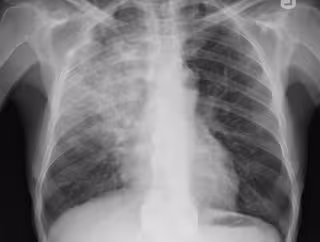

Neumonía, pulmonía, radiografía pulmones

Neumonía, pulmonía, radiografía pulmones - FLICKR/YALE ROSEN - Archivo